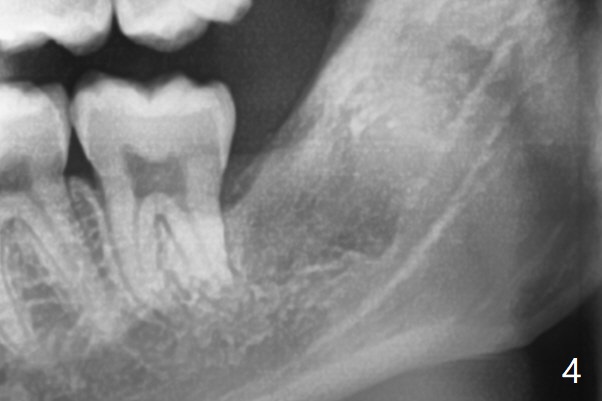

A 22-year-old man, asymptomatic, is going to have #1,16,17 and 32 extracted (Fig.1, fully bony impaction). For the large lower sockets (actually Buccal Impaction), collagen plug is placed in the inferior half, while Bone Cement (Bond Apatite from Augma (Fig.3 A)) and Osteogen plug (Fig.3 O) in the superior half at #32 and 17, respectively. Graft materials seem to spread into the lower haft of the sockets with apparent formation of new bone 4 months postop (Fig.4).